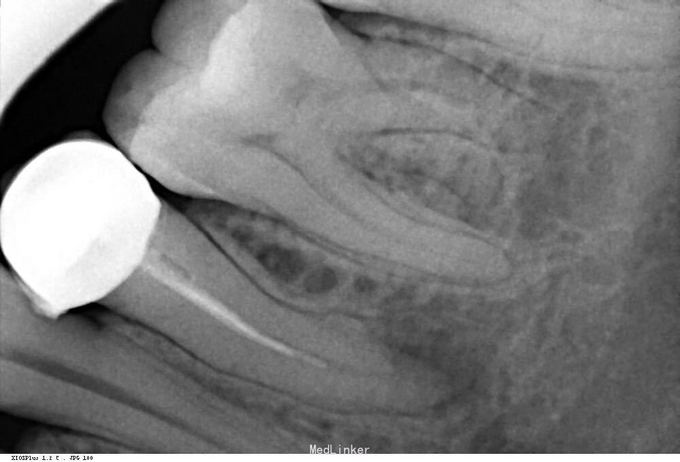

左下后牙咬物不适

左下后牙二年前治疗过,并已冠修复,近日咬硬物不适

35烤瓷冠,合面露金,轻微叩痛,牙龈无异常

根管再治疗,冠修复